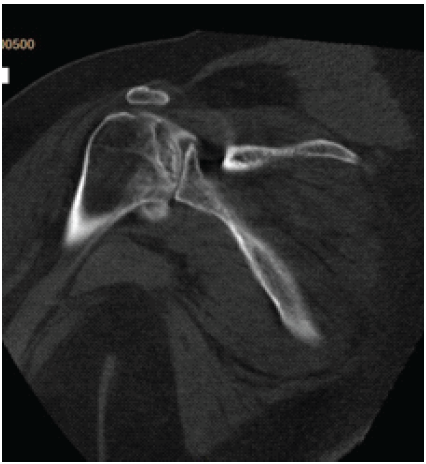

A 37-year-old woman with a body mass index (BMI) >40 presented to our orthopedic clinic in April 2024 for shoulder and hip pain. She was a non-smoker and denied drug and alcohol use. She reported first noticing joint pain in November 2023, approximately 2 years and 4 months after a severe COVID-19 infection in July 2021. Her COVID-19 disease process was complicated by asystole, acute kidney injury (AKI), shock liver, and acute encephalopathy. In the hospital, her AHRF was managed with intubation and a cumulative dose of 1640 mg of steroids. Before COVID-19, her past medical history included Class III obesity, prediabetes, polycystic ovarian syndrome, hypertriglyceridemia, hypertension, chronic bronchitis, anxiety, and depression. She was taking no chronic steroids; her bronchitis was managed with albuterol and montelukast. Initially, the patient’s COVID-19 infection was diagnosed at the pharmacy, but she later presented to the emergency department for respiratory distress, where 2 days of 20 mg of prednisone were prescribed. Due to worsening symptoms, the patient was then hospitalized for AHRF and received 40 mg of methylprednisolone twice per day. After succinylcholine administration for intubation, she went asystolic and needed cardiopulmonary resuscitation. After reanimation, transesophageal echocardiography showed a transient cardiomyopathy with reduced ejection fraction at 45–50%. Laboratory values showed elevated D-dimer levels, peaking at 17.73 mg/L (normal <0.5 mg/L), and elevated inflammatory markers, specifically an interleukin-6 of 56.54 pg/mL (normal <7.01 pg/mL), C-reactive protein of 279.30 mg/L (normal < 5 mg/L), and procalcitonin of 0.11 ng/mL (normal <0.1 ng/mL). During hospitalization, creatinine levels increased, indicating AKI; her alanine transaminase rose to 1318 U/L, indicating shock liver. She was also diagnosed with acute encephalopathy, evidenced by abrupt neurological changes, disorientation, reduced concentration, and slow speech. Overall, she spent 27 days in the hospital and received 1640 mg of steroids. After discharge, she received rehabilitative care at a nursing home. In November 2023, approximately 2 years and 4 months after being admitted for COVID-19, she was referred to rheumatology by her primary care physician for hip, knee, and shoulder joint pain of unknown etiology. With a history of metabolic encephalopathy overlying preexisting anxiety and depression, radiographic imaging without osseous findings, a positive antinuclear antibody, and no other rheumatological biomarkers, the rheumatologist diagnosed her with fibromyalgia. In March 2024, she was referred to a bariatric arthroplasty clinic for worsening hip pain and new-onset numbness and tingling. At the clinic visit, she had a positive Stinchfield test, and she reported a previous magnetic resonance imaging (MRI) of her left knee that had shown evidence for bone infarcts. Radiographic imaging of the hips was performed, showing bilateral AVN with collapse of the left femoral head. The patient was told that total joint arthroplasty was not an option at that time due to her elevated BMI and inflammatory markers. In April 2024, her primary care physician referred her to our orthopedic clinic for joint aspiration and intra-articular steroid injections. At that time, she was barely able to walk and also complained of increasing shoulder pain. Physical examination showed bilateral pain on palpation over the greater trochanters and the biceps tendons; she had a positive apprehension test and reduced shoulder range of motion. In April 2024, bilateral hip fluid aspiration with intra-articular steroid injections was performed. No marked effusions were found, and fluid cultures failed to show growth. Pain relief from the steroid injection lasted 2 weeks. Being a poor surgical candidate, in June 2024, bilateral femoral head core decompressive surgery was performed to try to delay total hip arthroplasty (THA) by improving interosseous blood flow. Due to continued pain, in August 2024, the shoulders and hips were imaged. Radiographs of the hips indicated no improvement of AVN despite decompressive surgery; there was Ficat-Arlet stage IV AVN bilaterally with crescentic sclerosis and bilateral femoral head collapse with greater collapse of the left femoral head (Fig. 1). Bilateral computed tomography angiography of the shoulders showed AVN affecting 75% of the surface areas in the humeral heads bilaterally, bilateral tendinosis of supraspinatus and infraspinatus muscles, and some degenerative changes in the long head of the right biceps (Fig. 2 and 3).

Figure 2: Computed tomography image of the left shoulder of a 37-year-old woman with multifocal osteonecrosis. The image was obtained on August 21, 2024. At present, no interventions have been performed on the avascular necrosis in the patient’s shoulders.